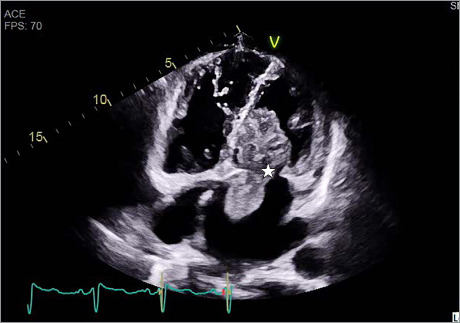

Cardiac myxomas are a rare phenomenon within the general population, and although there are reports of them, giant myxomas are not common in the medical literature. This report presents a case of a giant left atrial cardiac myxoma in a 57-year-old female patient who was largely asymptomatic until she presented with a diffuse thromboembolic stroke. This case report highlights the importance of surgical management of cardiac myxomas and discusses the difference in open vs minimally invasive surgical resection of giant cardiac myxomas.

Abstract Image